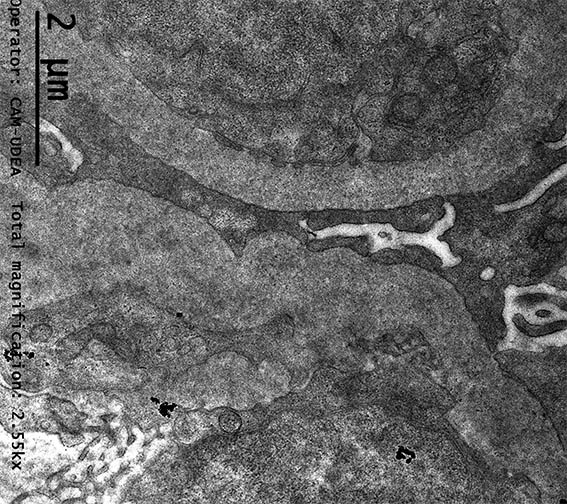

Figura 14. Microscopía electrónica, aumento original, X2.550. Observe un doble contorno en la pared del capilar de la parte inferior.

Figura 15. Microscopía electrónica, aumento original, X2.550. Observe depósitos electron-densos subendoteliales y daño podocitario extenso.

Figura 16. Microscopía electrónica, aumento original, X2.550. Membrana basal irregular, ondulada, posiblemente con doble contorno y depósitos electron-densos.

Figura 17. Microscopía electrónica, aumento original, X2.550. Observe depósitos electron-densos subendoteliales.